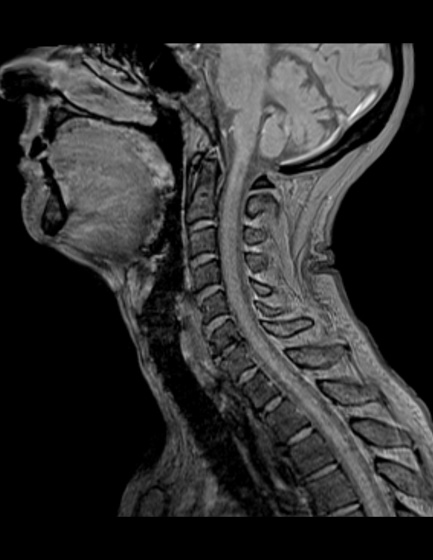

MRIとは、(MRI=MagneticResonanceImaging:磁気共鳴画像診断装置)の略です。MRIは、強力な磁石でできた筒の中に入り、強い磁石とラジオに使われているような電波を用いて体内の状態を画像にする検査です。特に脳や脊椎、四肢、子宮、卵巣、前立腺といった骨盤内の病変に関して優れた検出能力を持っています。

| 撮影可能な部位 | 頭部、脊椎、乳腺、腹部、骨盤部、関節など 全身領域 |

MRI検査依頼書(PDF)当院で撮影したMRI画像